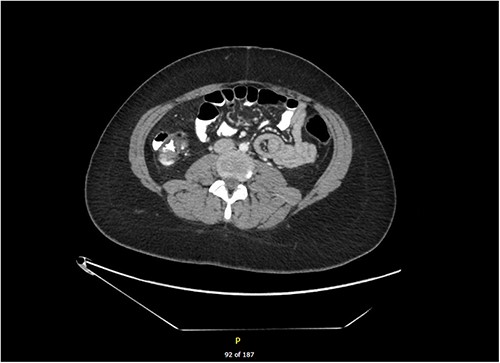

We present the case of a 20-year-old female who presented to the Emergency Department complaining of a 1-day history of sudden onset right iliac fossa pain associated with nausea and vomiting. On examination, her abdomen was soft with tenderness to palpation of the right iliac fossa and suprapubic regions. Her background history consisted of bipolar affective disorder, for which she was taking mirtazapine and aripiprazole. Bloods taken at the time of admission revealed an acute inflammatory process with white cells of 24.5 and a C-reactive protein (CRP) of 76.8. She was referred to the surgical team for work-up of acute appendicitis. She had a pelvic ultrasound to rule out any gynaecological cause of her pain, which showed normal appearance of the uterus and ovaries and was unable to visualize the appendix. She then proceeded to have a CT of her abdomen and pelvis which showed an 8 cm jejunal small bowel intussusception, with no focal bowel lesions or abnormalities within the surrounding mesentery identified (Fig. 1).

In our case, only one of the six intussusceptions was identified on CT. There is currently only one other documented case in the literature of such a high number of concurrent intussusceptions, which describe a 25-year-old male with underlying coeliac disease found to have five intussusceptions within the small bowel [6]. In any patient presenting with multiple or recurrent intussusceptions, a diagnosis of Peutz–Jeghers Syndrome must be considered. Peutz–Jeghers Syndrome is an autosomal dominant mutation in the STK11 gene characterized by gastrointestinal polyposis, mucocutaneous pigmentation, and cancer predisposition [7]. Typically, one of the hamartomatous polyps present in the small bowel will serve as a lead point for intussusception. Our patient, however, did not have Peutz–Jeghers and had no predisposing factors or identifiable lead points contributing to intussusception.

Whilst the CT scan only revealed one of the six intussusceptions, this finding was sufficient to bring the patient to theatre for reduction, consequently allowing for discovery and reduction of all six points. Small bowel intussusception may result in small bowel obstruction or bowel ischaemia requiring resection, fortunately our patient did not have features of either. Given that our patient’s intussusceptions were found to be idiopathic, laparoscopic reduction without resection was deemed an appropriate treatment [3].